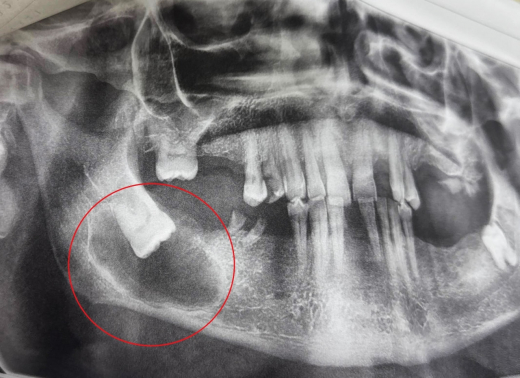

Неприятный сюрприз обнаружили врачи областной стоматологической поликлиники в Воронеже у пожилого пациента. 65-летний мужчина пришёл к медикам с жалобами на боли в челюсти. Видимых признаков каких-либо повреждений не было. Наблюдалась лишь небольшая припухлость в месте, где должен был располагаться зуб мудрости. Рентген показал причину болей. Зуб мудрости рос в кости горизонтально, а вокруг него ткани стали менее плотными и более пористыми. Также мелики предположили, что вокруг зуба образовалась киста. Как рассказали врачи в группе Минздрава во «ВКонтакте», лечение проводилось в несколько этапов. Стоматолог-хирург Анастасия Асеева сначала отслоила слизистую, затем сделала трепанацию кости, а далее удалила и сам зуб. Вмешательство проводили под местной анестезией. Послеоперационный период протекал гладко, рана зажила, швы сняли на 14 день. Пациент уже выписан. Врачи напоминают, что зубы мудрости часто становятся причиной челюстных заболеваний. Воронежцам стоит до каких-либо симптомов выяснить, есть ли не прорезавшиеся зубы и несут ли они какую-то угрозу.